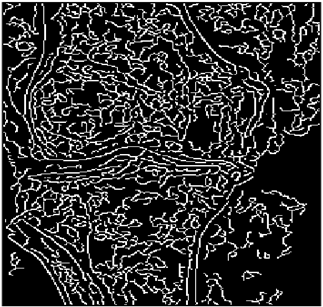

5. Results and Discussions

For the purpose of simulation, we consider two sets of images: (1) three images from MATLAB repository (Table 4) and (2) five X-ray images available online (Table 5).

As shown in Table 6, the PFOM values related to the smooth composition are higher than those of the standard composition in all cases. Table 7, Table 8, Table 9, Table 10, Table 11, Table 12, Table 13 and Table 14 also provide a visual demonstration supporting this conclusion. As is quite obvious from these tables, the density of noise in the edge-detected images of smooth composition is always less than that of the standard composition. Furthermore, the Canny edge detector is also highly prone to noises and is unable to decrease the noise density.

Table 14 shows the following:

• In all cases, the Canny edge detector detects more edge pixels than both fuzzy compositions.

• As the level of noise increases, all three methods become adversely affected by the noise, and still more edges are detected by Canny; however, most of the detected edges by Canny are misdetections due to the impact of noise. As is obvious from this table, the standard composition as well as the smooth composition somehow show equal performance in reducing noise density.

• However, in all cases, the PFOM value for the smooth composition is always greater than the PFOM value for the standard composition, according to Table 6.

Table 14. Edge-detected image of “X-ray 5” after binarization for different noises.

NoiseCannyStandardSmooth

No noise Mathematics 10 02421 i156 Mathematics 10 02421 i157 Mathematics 10 02421 i158

G(0.001) Mathematics 10 02421 i159 Mathematics 10 02421 i160 Mathematics 10 02421 i161

G(0.002) Mathematics 10 02421 i162 Mathematics 10 02421 i163 Mathematics 10 02421 i164

G(0.003) Mathematics 10 02421 i165 Mathematics 10 02421 i166 Mathematics 10 02421 i167

I(0.25%) Mathematics 10 02421 i168 Mathematics 10 02421 i169 Mathematics 10 02421 i170

I(0.5%) Mathematics 10 02421 i171 Mathematics 10 02421 i172 Mathematics 10 02421 i173

I(1%) Mathematics 10 02421 i174 Mathematics 10 02421 i175 Mathematics 10 02421 i176